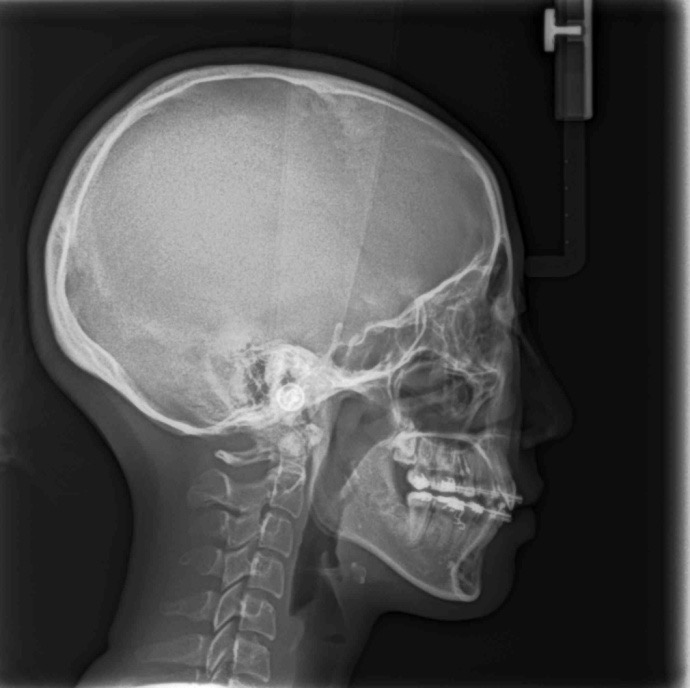

_PRE-TXNorm FMIA°47°55.0SNA°77.7°83.0SNB°70.2°80.0ANB°7.5°3.0FMA° 29.826PFH/AFH70.5°70Z Angle°50.3°77U1-FH113.0110.0IMPA°103.297.0U Lip to s’ line6.3 mm5.0L Lip to s’ line3.9 mm3.0OP-FH1215

头侧位片:

▲下颌后缩,骨性Ⅱ类

▲高角,颏部发育不足

▲上下前牙唇倾

Post-TXPRE-TXPost-TXNormFMIA°47°57.555.0SNA°77.7°76.883.0SNB°70.2°73.780.0ANB°7.5°3.13.0FMA° 29.828.026PFH/AFH70.5°65.970Z Angle°50.3°64.477U1-FH113.0103.7110.0 IMPA°103.291.197.0U Lip tos’ line6.3 mm3.25.0L Lip to s’ line3.9 mm1.03.0OP-FH1212.615